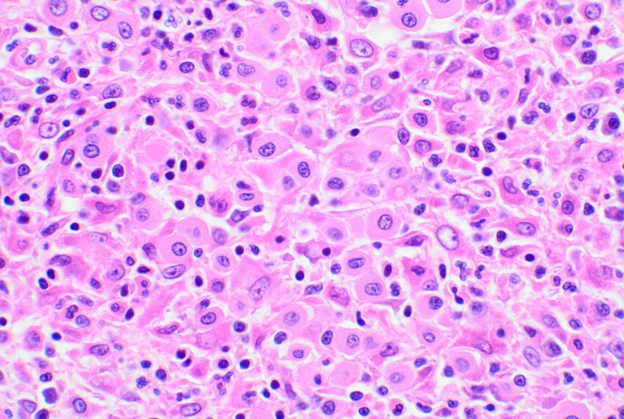

猫のcMCTは、細胞の特徴によって高分化型(図1)、非定型(または組織球型)(図2)、多形型(図3)、に分類されます。非定形型あるいは多形型のものは一見腫瘍細胞に異型性があるようですが、組織型と予後に有意な関連は今のところ報告されていません。そのため、病理組織学的に高分化型であっても必ずしも予後が良いとは限らず、低分化型のMCTであっても必ずしも予後が悪いわけではないという点に注意が必要です。また経験上、猫のcMCTでは、犬と比較して好酸球の浸潤に乏しく、病巣内に小型リンパ球の集簇巣がみられる場合が多いようです。

図3 多形型